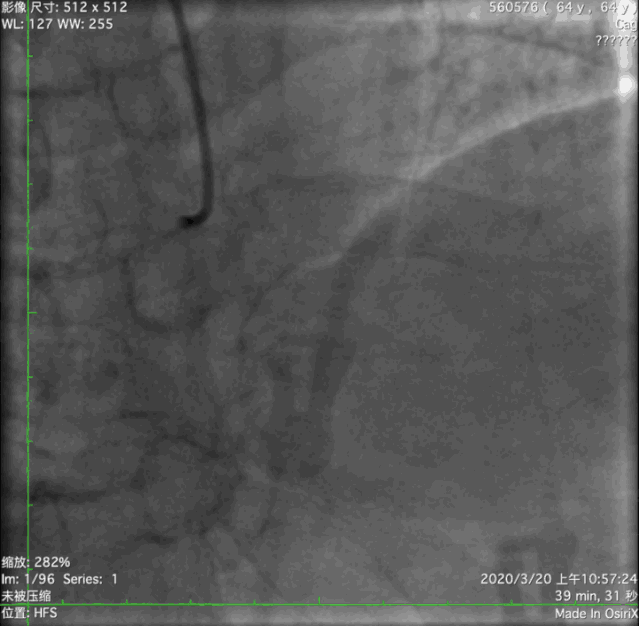

冠状动脉造影

RCA-PLA弥漫长病变,50%~80%狭窄。

介入治疗——预处理1

右桡动脉入路, 6F AR1.0 导引导管, BMW PTCA导丝。

2.5-20mm半顺应性球囊以10ATM扩张RCA-PLA靶病变,狭窄减轻,未见夹层。